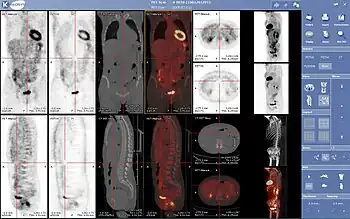

La medicina nuclear es una especialidad de la medicina[1] en la que se utilizan radiotrazadores o radiofármacos (formados por un fármaco transportador y un isótopo radiactivo) para el diagnóstico y tratamiento de enfermedades. Estos radiofármacos se aplican dentro del organismo humano por diversas vías (la más utilizada es la vía intravenosa). Una vez que el radiofármaco está dentro del organismo, se distribuye por diversos órganos dependiendo del tipo empleado. La distribución de este es detectado por un aparato detector de radiación llamado gammacámara y almacenado digitalmente. Luego se procesa la información obteniendo imágenes de todo el cuerpo o del órgano en estudio. Estas imágenes, a diferencia de la mayoría de las obtenidas en radiología, son imágenes funcionales y moleculares, es decir, muestran cómo están funcionando los órganos y tejidos explorados o revelan alteraciones de los mismos a un nivel molecular.

Se utiliza para diagnosticar y determinar la gravedad y tratamiento de una o varias enfermedades, incluyendo cáncer en diversos tipos, enfermedades cardíacas, gastrointestinales, endocrinas, desórdenes neurológicos, y otras anomalías dentro del cuerpo. Debido a que los procedimientos de medicina nuclear pueden detectar actividades moleculares dentro del cuerpo, ofrecen la posibilidad de identificar enfermedades en sus etapas tempranas, así también como las respuestas inmediatas de los pacientes a las intervenciones terapéuticas.